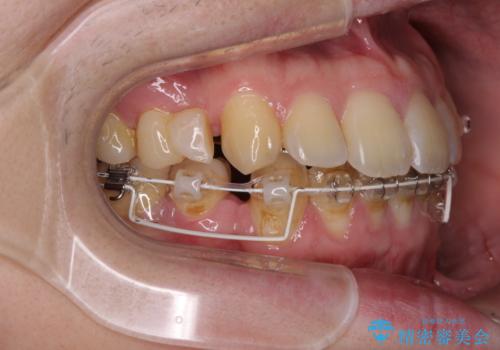

出っ歯と八重歯 目立たない裏側装置でスッキリとした口元に

- ハーフリンガル

- 上顎の前突感による口の閉じにくさと八重歯を気にして来院された患者様です。

目立たない装置を希望されたので、上顎が裏側装置のハーフリンガルを選択し、上下左右の小臼歯(計4歯)を抜歯して矯正治療を行うこととしました。

上下顎で左右差の大きい抜歯矯正を裏側装置で行ったため、非常に時間がかかりましたが、正中位置も良い位置に改善され、気になっていた突出感も解消されました。